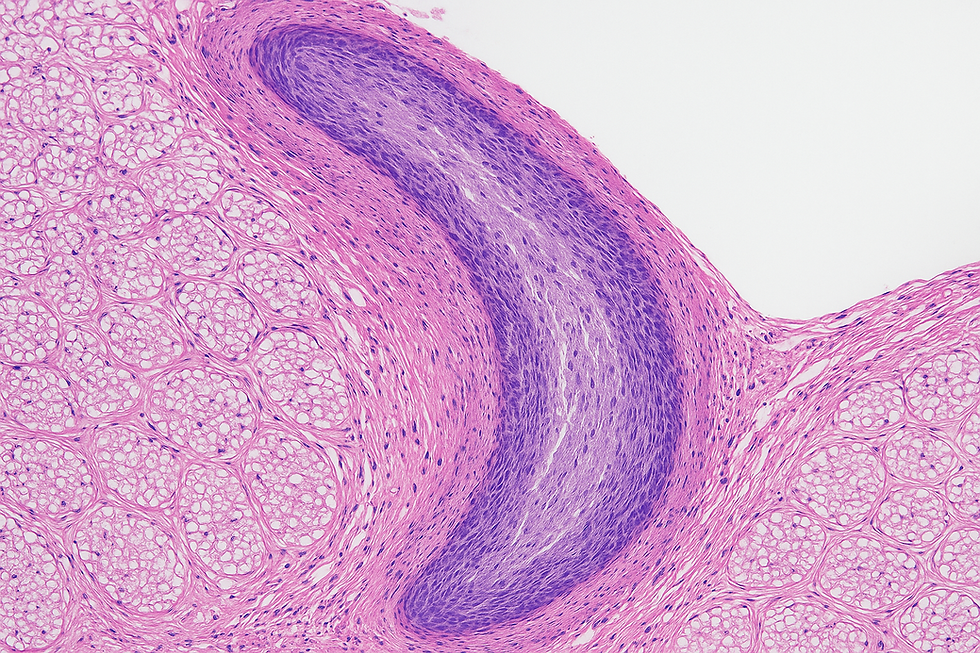

La enfermedad de Peyronie ocurre cuando se forman placas de tejido cicatricial (fibrosis) en la túnica albugínea del pene. Esto provoca: